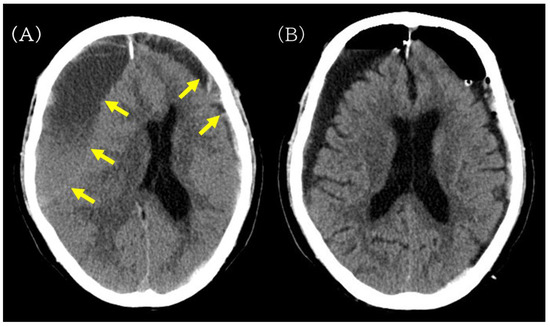

Figure 2.

Preoperative and postoperative non-contrast head CT images illustrating hematoma evacuation after burr-hole drainage. (A) Preoperative non-contrast head CT showing bilateral chronic subdural hematomas (yellow arrow), more prominent on the right, compressing both cerebral hemispheres. (B) Postoperative head CT obtained after burr-hole drainage showing reduced hematoma volume without new intracranial hemorrhage.

On the day of admission (postoperative day [POD] 0), right-sided burr-hole drainage of the CSDH was performed. The procedure was uneventful, and postoperative head CT confirmed adequate hematoma evacuation without new hemorrhage or acute brain swelling (Figure 2B). Cefazolin was continued perioperatively (2 g/day on POD 0 and 4 g/day on POD 1–3).